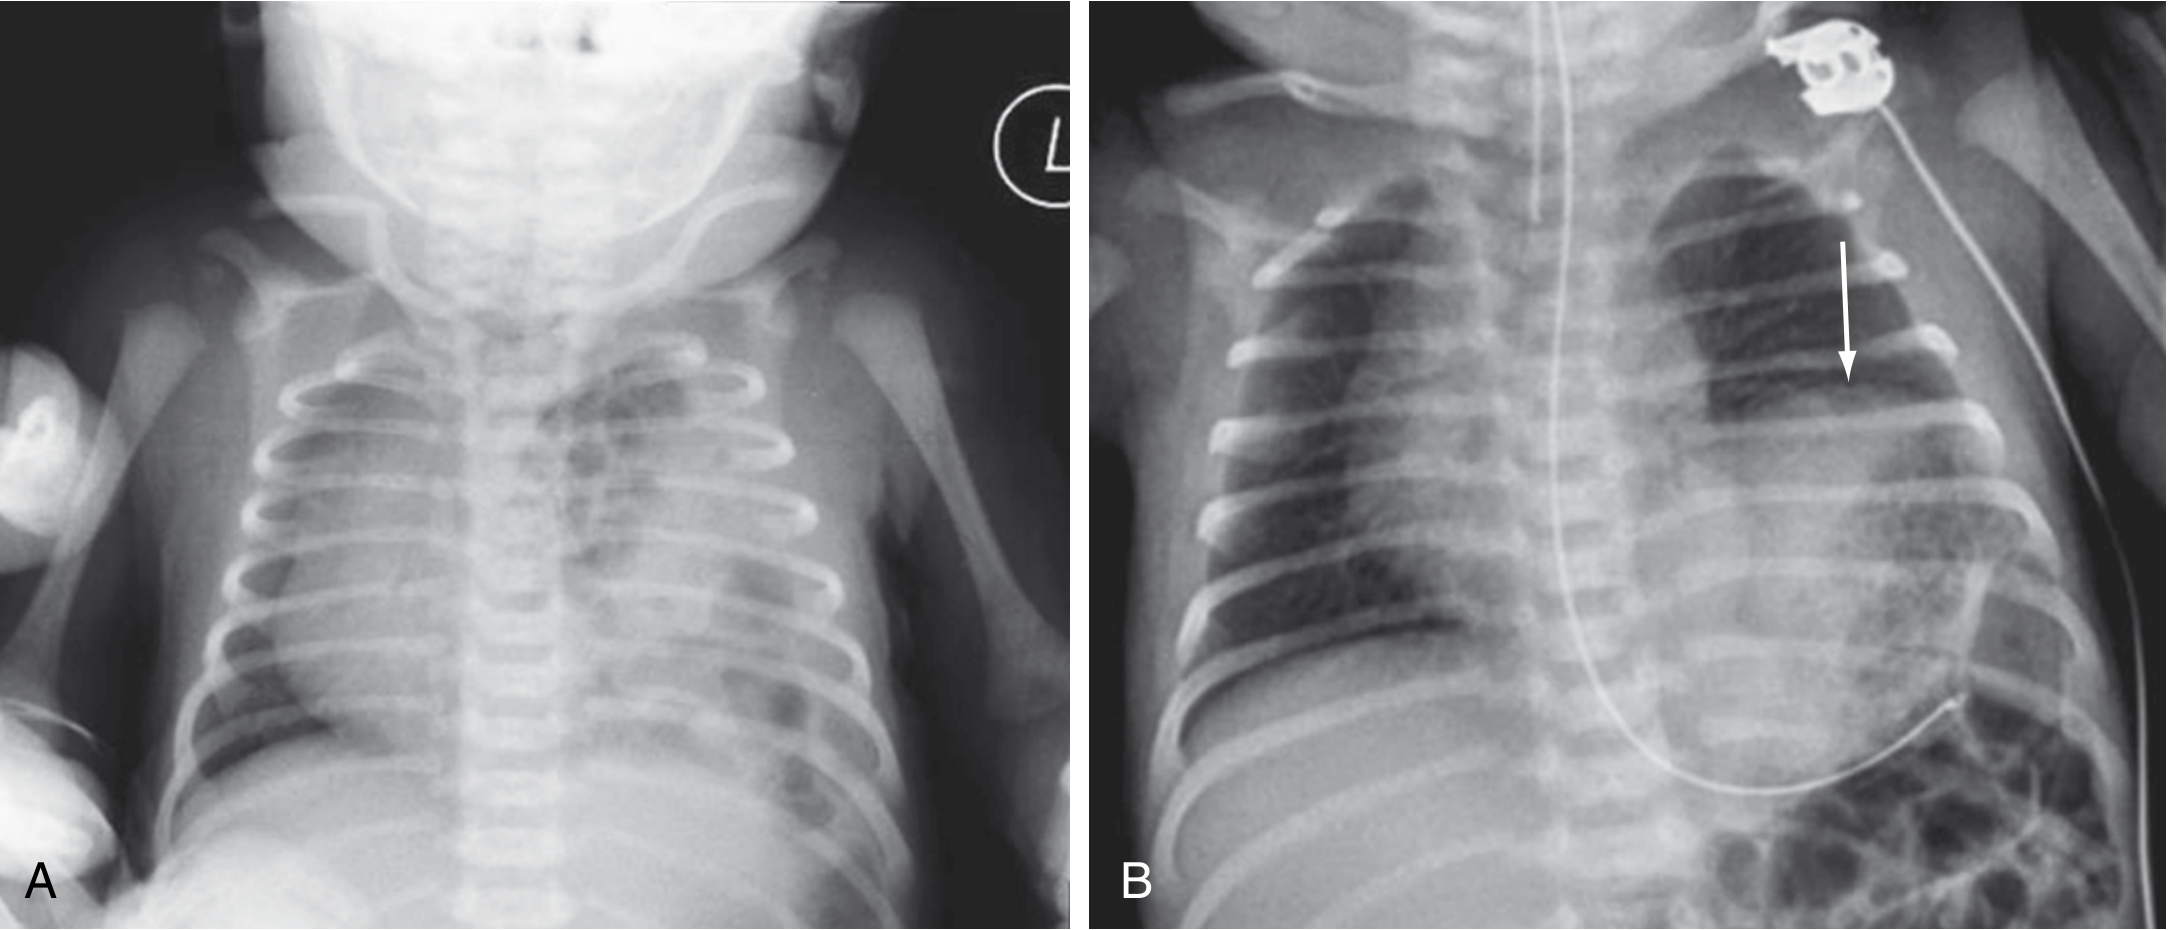

Chest X-Ray

CDH Chest X-ray and diaphragmatic eventration

(A) Multiple gas-filled bowel loops in the left hemithorax with rightward mediastinal shift — classic CDH. (B) Left diaphragmatic eventration (arrow) from phrenic nerve injury-induced paralysis. — Sabiston Textbook of Surgery, p. 2675